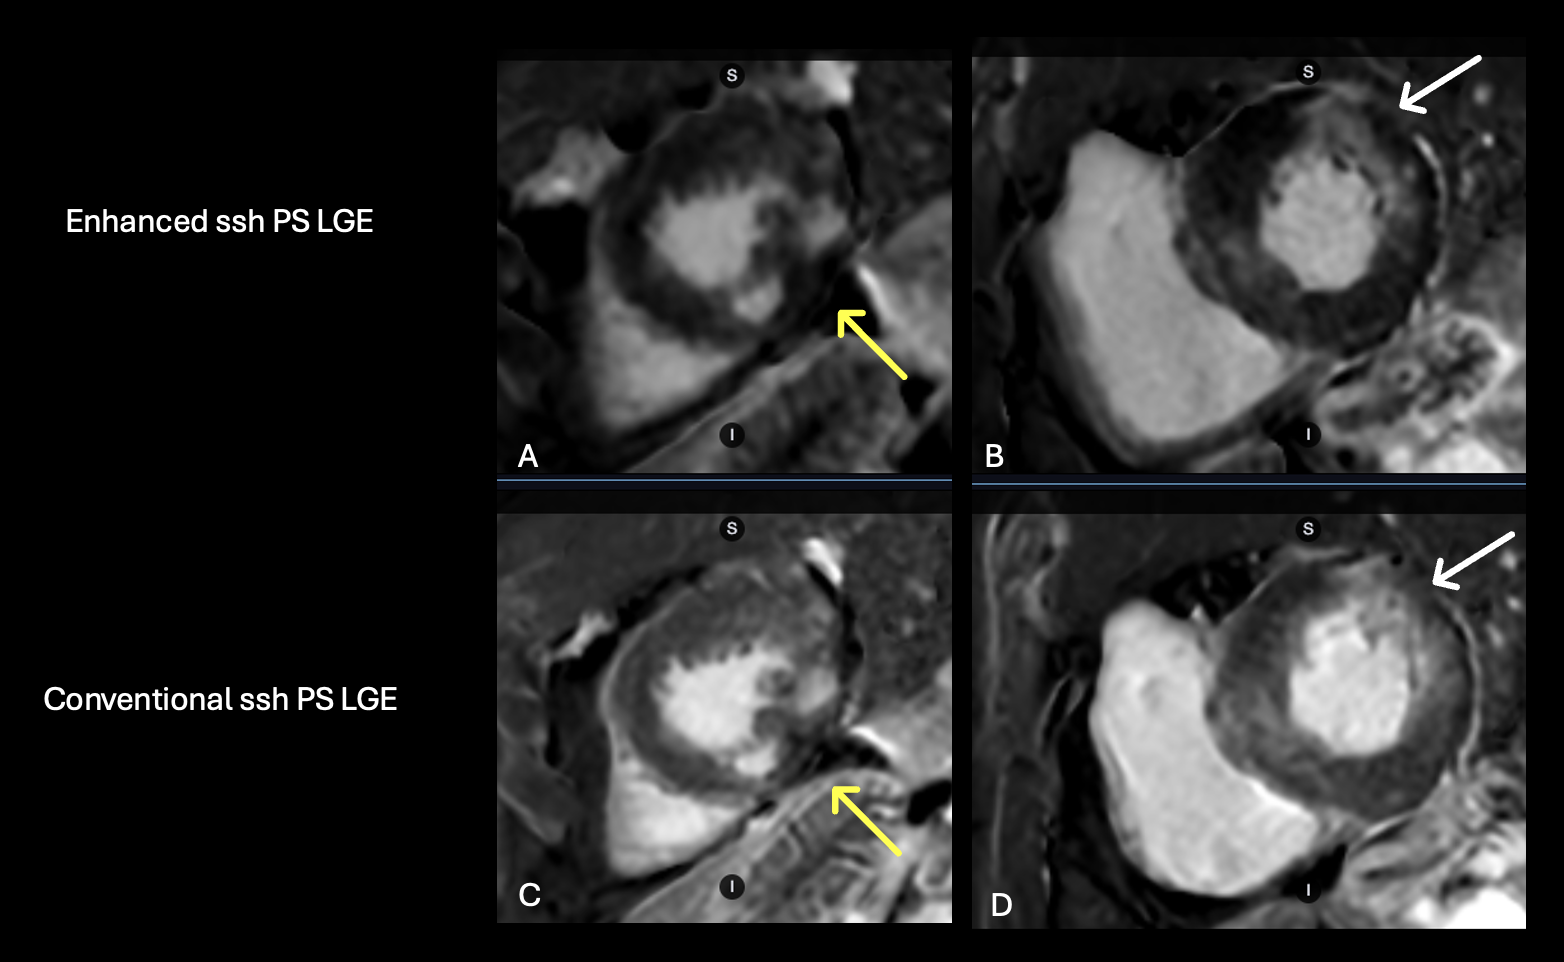

Figure 2. 83-year-old male patient with history of sarcoid referred for evaluation of non-sustained ventricular tachycardia. Ssh PS LGE acquired with the enhanced protocol (A) demonstrates improved image sharpness with better visualization of the inferolateral wall patchy midmyocardial delayed enhancement (yellow arrow) over conventional (C). Additional short axis image demonstrating patchy mid myocardial delayed enhancement within the mid anterolateral wall (white arrow) with improved image sharpness and less image blurring with the enhanced ssh PS LGE (B) over conventional (D).